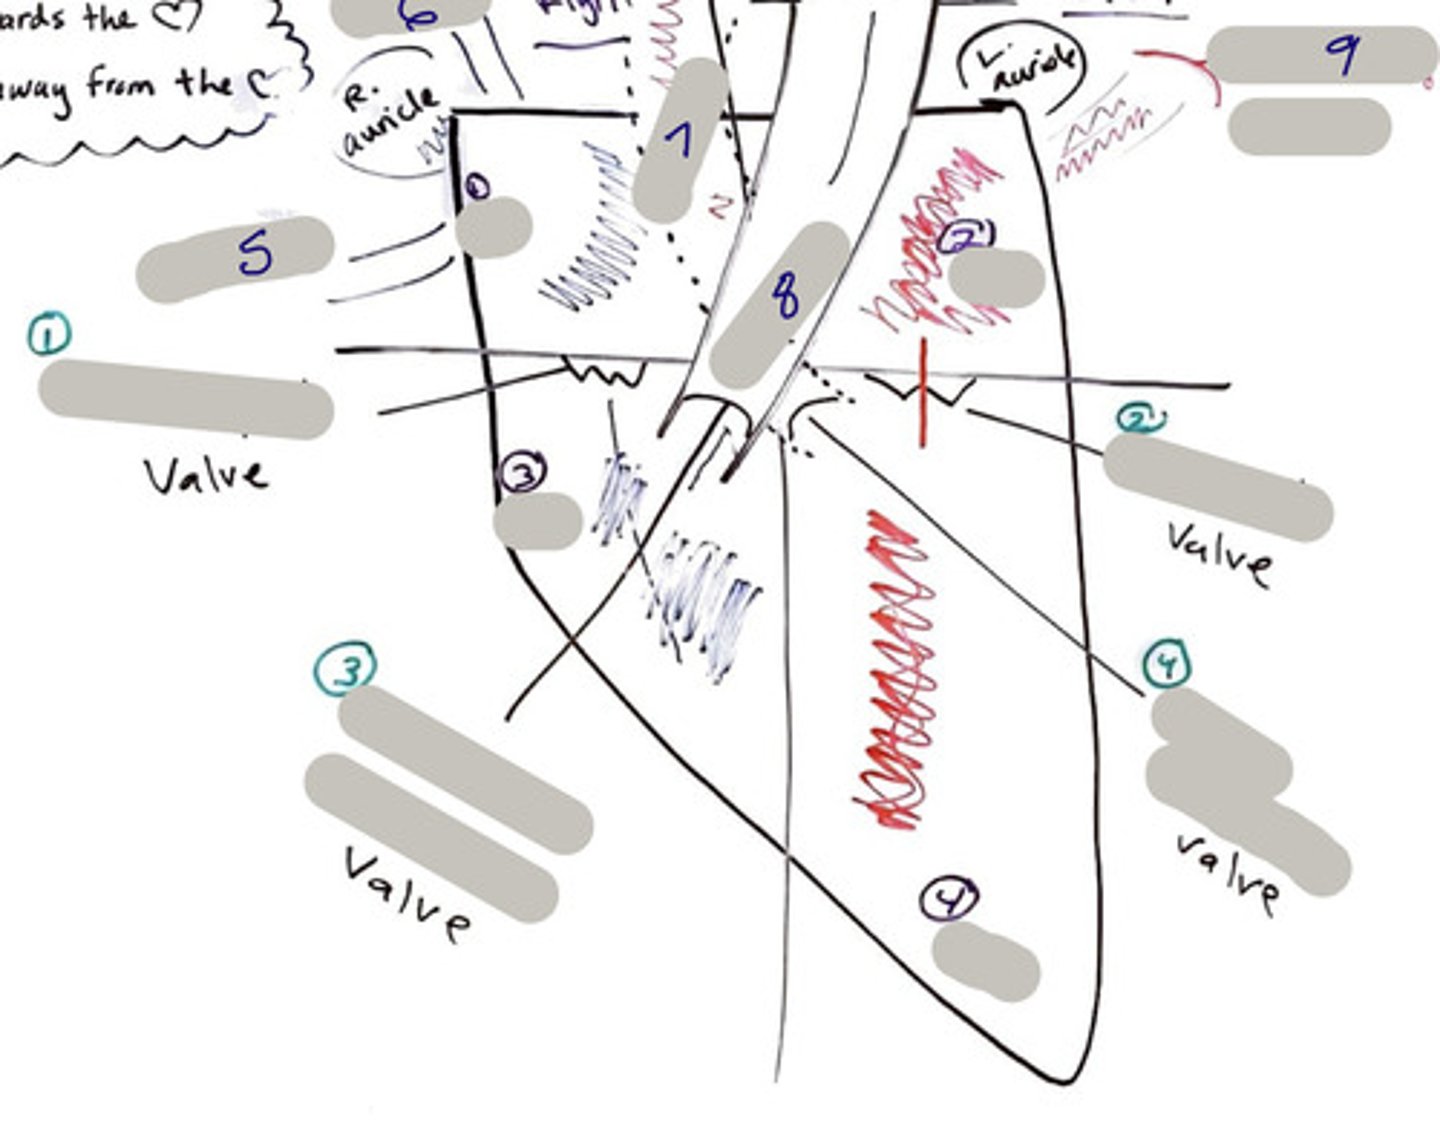

Tricuspid Valve (Right Atrioventricular Valve)

1-valve

Bicuspid valve (Left Atrioventricular Valve)

2-valve

Pulmonary Semilunar Valve

3-valve

Aortic Semilunar Valve

4-valve

Right Atrium

1-chamber

Left Atrium

2-chamber

Right Ventricle

3-chamber

Left Ventricle

4-chamber

Inferior Vena Cava

5-A vein that is the largest vein in the human body and returns blood to the right atrium of the heart from bodily parts below the diaphragm.

Superior Vena Cava

6-A vein that is the second largest vein in the human body and returns blood to the right atrium of the heart from the upper half of the body.

Aorta

7-The large arterial trunk that carries blood from the heart to be distributed by branch arteries through the body.

Pulmonary Trunk

8-carries blood from right ventricle to pulmonary arteries

Pulmonary veins

9-a vein carrying oxygenated blood from the lungs to the left atrium of the heart.